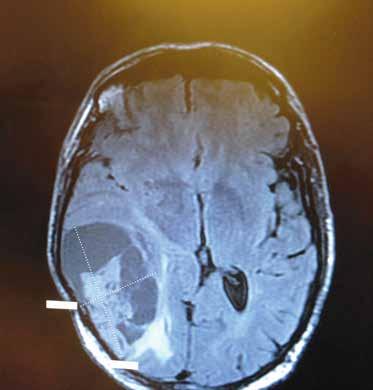

“The level of stroke care Cottage provided saved my life.”

Ric has always been active — an avid polo player, surfer and cyclist. One night, he suffered a stroke and was admitted to Santa Barbara Cottage Hospital. Upon his arrival, Ric could not move one side of his body — the stroke activation team began immediate treatment.

Ric made a full recovery and is back to his active life

COMPREHENSIVE STROKE PROGRAM

• Highest level of stroke care

• Multidisciplinary stroke team

• Award-winning program

To learn more about our stroke program and related services, please call Lauren Fink at 805-746-6195.

cottagehealth.org/stroketeam Ric, Stroke Survivor